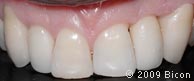

66. Вид интегрированной коронки (IAC).

67. Вид интегрированной коронки (IAC).

68. Вид спереди.